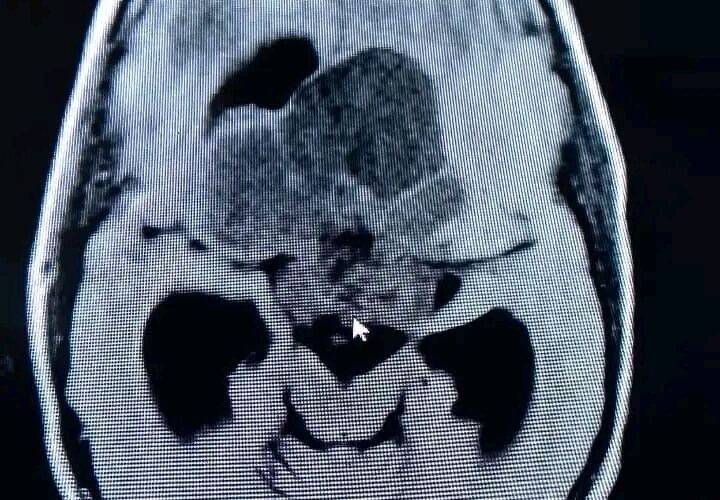

El pasado miércoles 15 de enero los especialistas en neurocirugía Dr. Alberto Carrillo Comas y Dr. Abel Álvarez Armasi realizaron una intervención quirúrgica a un paciente de 10 años de edad con un tumor gigante que ocupaba toda la base de cráneo (por imagen impresionaba un craneofaringeomas).

El menor fue sometido a intervención quirúrgica en el Hospital Pediátrico Provincial Eliseo Noel Caamaño, con el objetivo de resecar todo el tumor y tratar la hidrocefalia que también padecía el paciente.

Después de seis horas de cirugía se logra resecar el tumor en su totalidad, además de tratar la hidrocefalia. En estos momentos el paciente se encuentra extubado, con una buena evaluación y notable mejoría de su estado neurológico.

En estos momentos el paciente se encuentra extubado, con una buena evaluación y notable mejoría de su estado neurológico. Foto: Tomada de Girón.